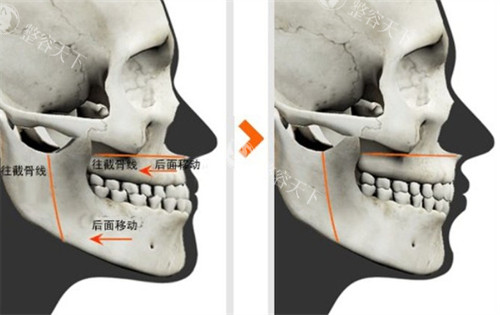

创新小创口技术体系何晋龙医生研发的"颌面小创口技术"采用三维智能化设计,通过微小切口完成骨骼重塑,出血量减少50%,肿胀程度降低40%。

个性化手术方案每位求美者都会接受CT三维扫描和面部力学分析,根据骨骼结构、软组织分布定制专属方案,避免"千人一面"。

病例背景28岁女性因下颌角外翻导致"国字脸",伴有明显不对称,经何医生采用"长曲线截骨术"矫正。

手术过程术中同步进行咬肌修薄和颊脂垫调整,手术时长2.5小时,出血量仅80ml。

修养结果术后3个月面部线条流畅自然,咬合功能完全正常,侧面轮廓提升30°。

术中流程划线设计→消毒麻醉→小创口入路→骨骼重塑→止血缝合,全程心电监护。